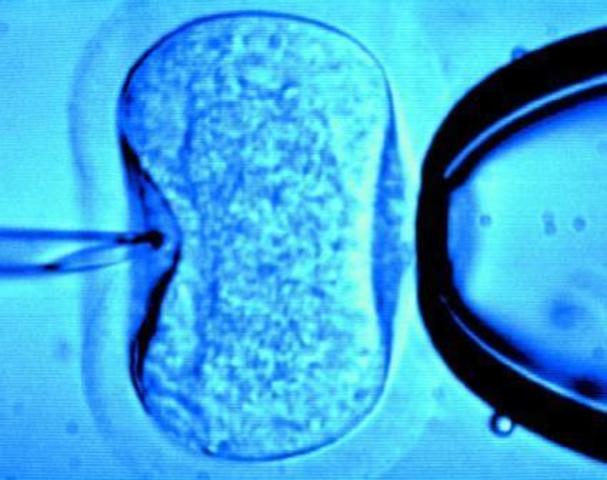

Consiste en fecundar el ovocito con el espermatozoide en el laboratorio.